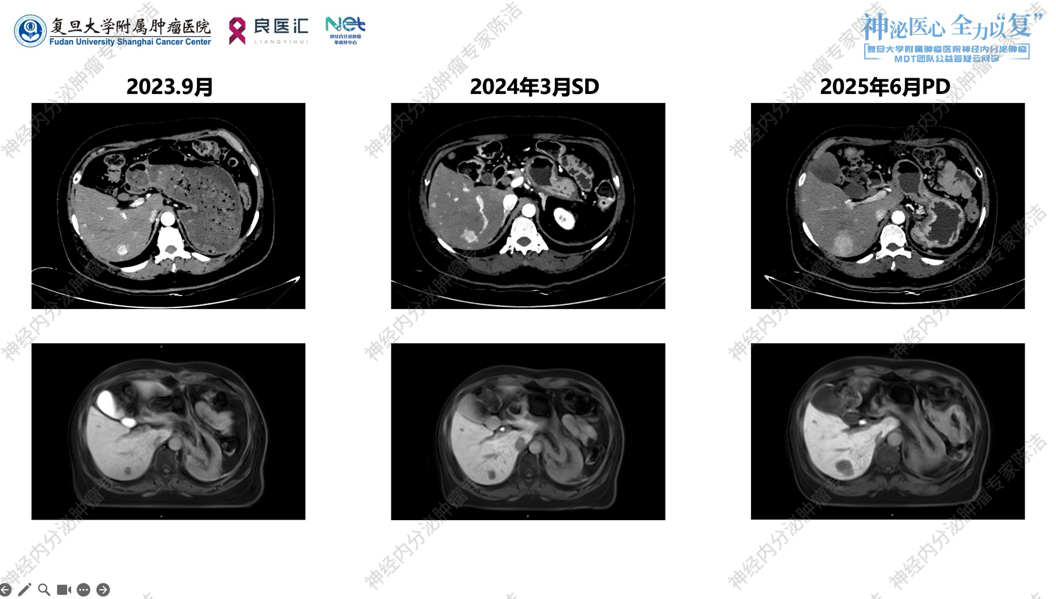

• 2023年9月:行基线增强CT及肝普美显MR后,开始长效奥曲肽30mg q4w。

• 2023年9月—2025年3月:定期复查,肿瘤评估为疾病稳定(SD)。

• 2025年6月:复查增强CT及肝普美显MR提示肝内病灶较前增多、增大,评估为疾病进展(PD)。

术后长效奥曲肽30mg q4w治疗,期间定期复查。至2025年6月,CT及MR图像均显示肝内散在的转移灶较2024年3月及2023年9月明显增多、增大,且血供丰富,属于明确的影像学PD状态。2025年11月MR评估,估计肝肿瘤负荷在20%—30%左右。